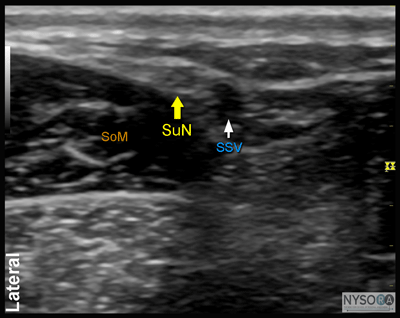

Figure 13: (A) Ultrasound anatomy of the sural nerve (SuN). The SuN is seen immediately anterior to the small saphenous vein (SSV). (B) The ultrasound anatomy of the SuN with the structures labeled. SoM, soleus muscle. ![]() Figure 14: Transducer position and needle position to block the saphenous nerve. Equipment Equipment needed includes the following:

Figure 7:Transducer position and needle insertion to block the superficial peroneal nerve. ![]() Figure 8: Cross-sectional anatomy of the superficial peroneal nerve (SPN). EDL, extensor digitorum longus muscle; PBM, peroneus brevis muscle. Superficial Peroneal Nerve The superficial peroneal nerve innervates the dorsum of the foot. It emerges to lie superficial to the fascia 10 to 20 cm above the ankle joint on the anterolateral surface of the leg. A transducer placed transversely on the leg, approximately 5 cm proximal and anterior to the lateral malleolus, will identify the hyperechoic nerve lying in the subcutaneous tissue immediately superficial to the fascia (Figures 7, 8, and 9A and B). If the nerve is not readily apparent, the transducer can be traced proximally on the leg until, at the lateral aspect, the extensor digitorum longus and peroneus longus muscles can be seen with a prominent groove between them leading to the fibula (Figure 10A and B). The superficial peroneal nerve is located in this intermuscular septum, just deep to the fascia. Once it is identified at this more proximal location, it can be traced distally to the ankle. Because the superficial nerves are rather small, their identification with ultrasound is not always possible in a busy clinical environment. Sural Nerve The sural nerve innervates the lateral margin of the foot and ankle. Proximal to the lateral malleolus, the sural nerve can be visualized as a small hyperechoic structure that is intimately associated with the small saphenous vein (Figures 11, 12, and 13A, B). A calf tourniquet can be used to increase the size of the vein, aiding in identification of the nerve. Saphenous Nerve The saphenous nerve innervates the medial malleolus and a variable portion of the medial aspect of the leg below the knee. The nerve travels down the medial leg alongside the saphenous vein. Because it is a small nerve, it is best visualized 10-15 cm proximal to the medial malleolus, using the saphenous vein as a landmark (Figures 14, 15, and 16A, B). A proximal calf tourniquet can be used to assist in increasing the size of the vein. The nerve appears as a small hyperechoic structure.